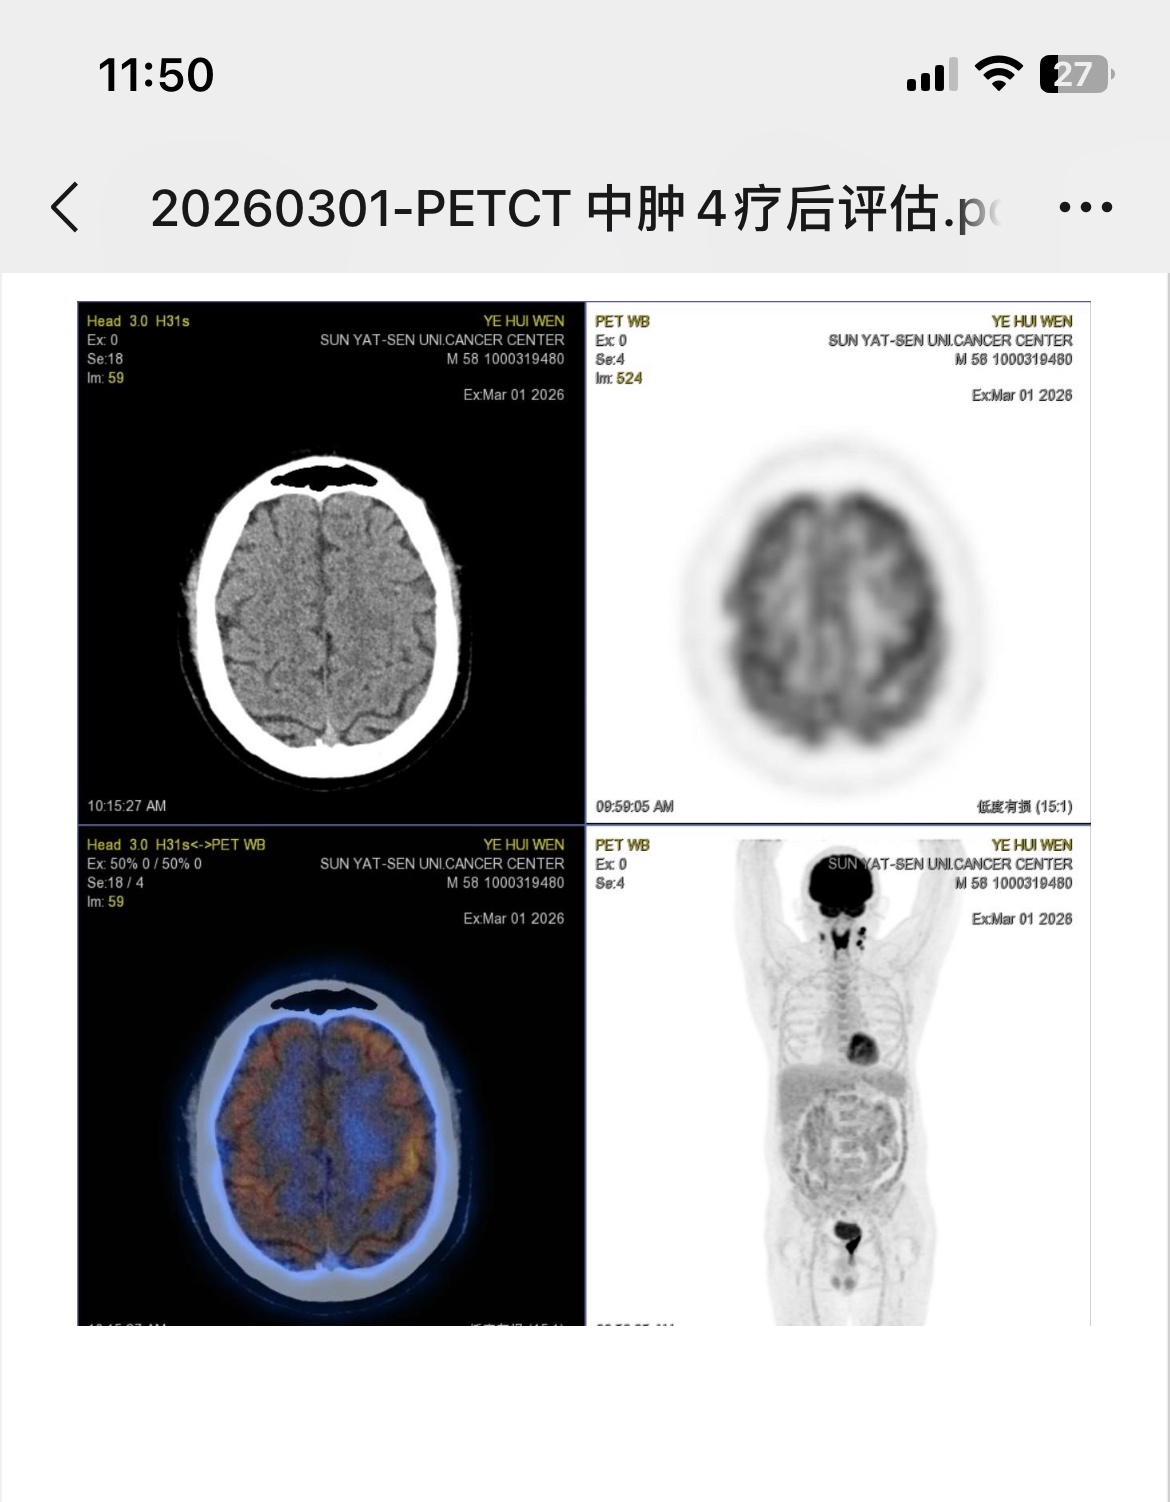

霍奇金混细,pd-1+avd进行了四个疗程后5分,医生觉得不着急换方案,打完剩余两个疗程?大神可以帮忙看看吗。@橙色雨丝

杨清明那边建议是bv+gemox,但主治不同意,认为做完六个疗程后再评估再决定